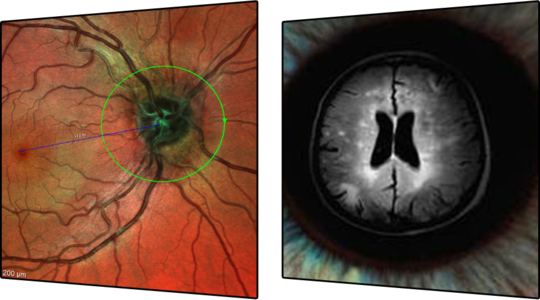

A Edição Premium do Módulo de Glaucoma SPECTRALIS® combina o exclusivo Sistema de Posicionamento Anatômico (APS) com uma série de padrões de varredura únicos para avaliar o disco óptico, a camada de fibras nervosas da retina e a camada de células ganglionares da mácula. Esses padrões de varredura baseados no APS são automaticamente ajustados aos marcos anatômicos exclusivos de cada olho e às características das finas estruturas anatômicas relevantes para o diagnóstico de glaucoma.

A Edição Premium do Módulo de Glaucoma compara os olhos dos pacientes a um banco de dados de referência de olhos normais, detectando até mesmo as pequenas variações. A precisão da função AutoRescan do SPECTRALIS permite a identificação e o monitoramento confiável de alterações estruturais ao longo das visitas, proporcionando um acompanhamento contínuo e preciso da progressão do glaucoma.

• Sistema de Posicionamento Anatômico (APS)

Combina o exclusivo Sistema de Posicionamento Anatômico (APS) com uma série de padrões de varredura únicos para avaliar o disco óptico, a camada de fibras nervosas da retina e a camada de células ganglionares da mácula. Esses padrões de varredura baseados no APS são automaticamente ajustados aos marcos anatômicos exclusivos de cada olho e às características das finas estruturas anatômicas relevantes para o diagnóstico de glaucoma.

A Edição Premium do Módulo de Glaucoma compara os olhos dos pacientes a um banco de dados de referência de olhos normais, detectando até mesmo as pequenas variações. A precisão da função AutoRescan do SPECTRALIS permite a identificação e o monitoramento confiável de alterações estruturais de uma visita para a outra.

• Cabeça do nervo Óptico

• Camada de Fibras Nervosas da Retina (RNFL)

• Polo Posterior

• Relatório de Glaucoma de Hood

• Mapas de Desvio

O poder de discriminação dos mapas de desvio permite visualizar a perda estrutural de forma rápida e clara. A comparação das medições de espessura com o banco de dados de referência (RDB) aumenta o valor diagnóstico dos mapas de espessura. Os mapas de desvio resultantes destacam a probabilidade de medições de espessura que não estão “Dentro dos Limites Normais”, revelando regiões e padrões associados dentro de camadas retinianas específicas que apresentam valores estatisticamente significativos mais finos ou mais espessos.